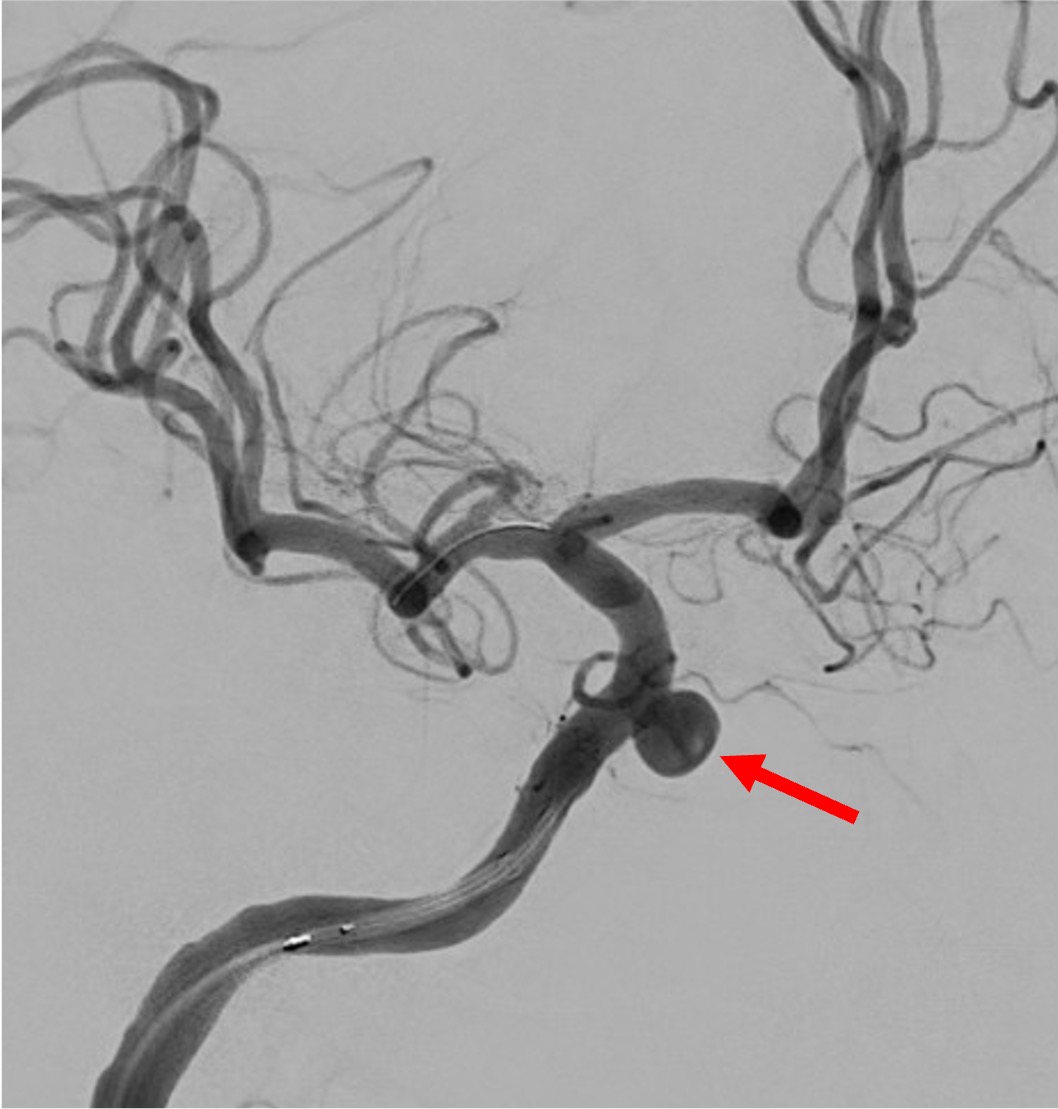

当院で行われた症例を提示いたします。80歳、女性、くも膜下出血の患者様。血管撮影にて図1〜4赤矢印の様に脳底動脈に広頸のネックを伴う不整形の瘤を認めました。母血管の蛇行狭窄が強く、マイクロカテーテルが複数入りにくい状態だったのでWEB(図5〜8黄色矢印)を用いて治療を行いました。術後MRAでも図10青矢印の様に動脈瘤は描出されません(図9は術前MRA)。現在も出血なく経過しております。

その1例を提示します。患者さんは65歳女性です。頭痛でMRIAを行い、血管撮影にて図1赤矢印の様に最大径7.8mm.ネック径4mmで、パイプラインというフローダイバーターステント(X線にて確認可能、図2〜5青矢印)を留置しました。その後、4ヶ月後の血管撮影ですが、図6緑矢印の様に動脈瘤は消失しています。